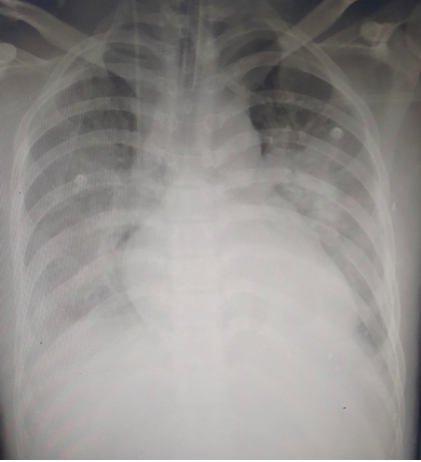

Tuy nhiên, bệnh nhân diễn biến rất nặng, huyết áp tụt sâu phải duy trì vận mạch liều cao, tổn thương phổi nặng. Bệnh nhân được chuyển Khoa Hồi sức tích cực – Chống độc điều trị trong tình trạng hôn mê, thở máy qua ống nội khí quản, huyết áp phụ thuộc vận mạch liều cao, tổn thương phổi nặng.

Mặc dù bệnh nhân đã được điều trị tối ưu, lọc máu liên tục, tuy nhiên, tình trạng oxy hóa máu chưa cải thiện được nhiều, SpO2 chỉ đạt tối đa 68% kèm theo huyết áp tụt sâu. Đứng trước tình huống đó, bệnh nhân đã được hội chẩn toàn khoa đưa ra chỉ định dùng kỹ thuật tim phổi nhân tạo (ECMO) để điều trị hỗ trợ tim phổi cho bệnh nhân.

Hình ảnh tổn thương phổi của bệnh nhân. Ảnh: BVCC